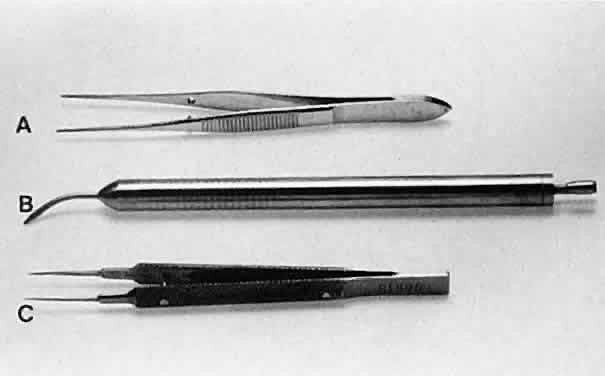

HOLDING INSTRUMENTS Microsurgery requires fine control of instruments. To achieve this control, the

surgeon must be familiar with the advantages of different instrument

designs. Some surgical instruments have a serrated flat handle, others

have a rounded knurled handle, and still others have a round

serrated handle (Fig. 11). The serrated or knurled areas allow the surgeon a firmer grasp and tighter

control of the surgical instrument. An instrument with a round, knurled

handle may be rotated in the fingertips, allowing for greater

flexibility during some procedures. For example, some types of tying

forceps are designed with this option. In contrast, most ocular scissors

have a flat serrated handle.  Fig. 11. Three surgical instruments with three handle styles. A. A flat serrated handle. B. A round serrated handle. C. A round knurled handle. Fig. 11. Three surgical instruments with three handle styles. A. A flat serrated handle. B. A round serrated handle. C. A round knurled handle.